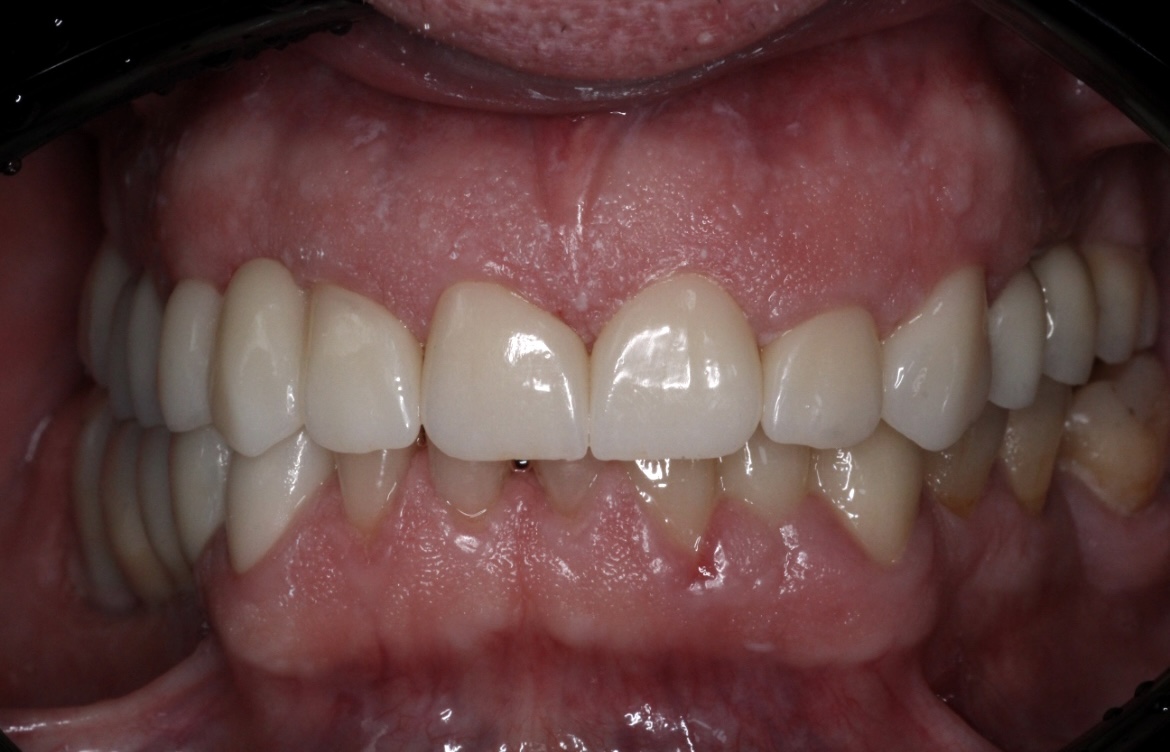

Наши работы